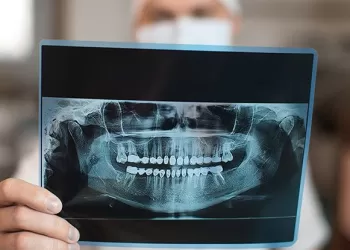

Panoramik Film Ne İçin ve Nasıl Çekilir?

Panoramik film ne için ve nasıl çekilir? Panoramik film ağızda gözle görünmeyen problemlerin tespit edilebilmesi amacıyl...